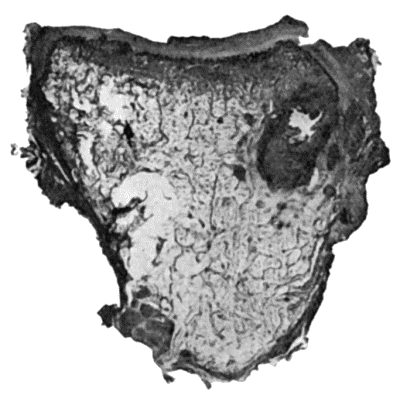

114.Section through Gouty Bursa 428

The introduction of a colony of micro-organisms is quickly followed by an accumulation of wandering cells, and proliferation of connective-tissue cells in the tissues at the site of infection. The various cells are attracted to the bacteria by a peculiar chemical or biological power known as chemotaxis, which seems to result from variations in the surface tension of different varieties of cells, probably caused by some substance produced by the micro-organisms. Changes in the blood vessels then ensue, the arteries becoming dilated and the rate of the current in them being for a time increased—active hyperæmia. Soon, however, the rate of the blood flow becomes slower than normal, and in course of time the current may cease (stasis), and the blood in the vessels may even coagulate (thrombosis). Coincidently with these changes in the vessels, the leucocytes in the blood of the inflamed part rapidly increase in number, and they become viscous and adhere to the vessel wall, where they may accumulate in large numbers. In course of time the leucocytes pass through the vessel wall—emigration of leucocytes—and move towards the seat of infection, giving rise to a marked degree of local leucocytosis. Through the openings by which the leucocytes have escaped from the vessels, red corpuscles may be passively extruded—diapedesis of red corpuscles. These processes are accompanied by changes in the endothelium of the vessel walls, which result in an increased formation of lymph, which transudes into the meshes of the connective tissue giving rise to an inflammatory œdema, or, if the inflammation is on a free surface, forming an inflammatory exudate. The quantity and characters of this exudate vary in different parts of the body, and according to the nature, virulence, and location of the organisms causing the inflammation. Thus it may be serous, as in some forms of synovitis; sero-fibrinous, as in certain varieties of peritonitis, the fibrin tending to limit the spread of the inflammation by forming adhesions; croupous, when it coagulates on a free surface and forms a false membrane, as in diphtheria; hæmorrhagic when mixed with blood; or purulent, when suppuration has occurred. The protective effects of the inflammatory reaction depend for the most part upon the transudation of lymph and the emigration of leucocytes. The lymph contains the opsonins which act on the bacteria and render them less able to resist the attack of the phagocytes, as well as the various protective antibodies which neutralise the toxins. The polymorph leucocytes are the principal agents in the process of phagocytosis (p. 22), and together with the other forms of phagocytes they ingest and destroy the bacteria.